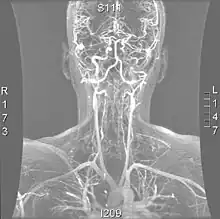

| Arteries of the neck, with arrows indicating the right vertebral artery | |